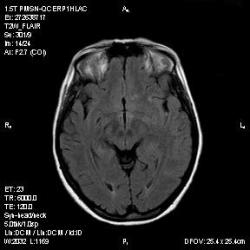

Из анамнеза - Женщина 45 лет. За год похудела на 15 кг (со слов матери), в последние месяцы случались эпизоды потери сознания. Онкозаболеваний и прочая в анамнезе нет. Сознание спутанное, из особенностей в анализах только подъем амилазы крови.

"Раскрою" карты. Мы подумали о синдроме MELAS (mitochondrial encephalomyopathy, lactic acidosis and stroke) - дословно, митохондриальная энцефаломиелопатия, лактоацидоз и инсульт. В качестве дифференциальной диагностики можно было бы предположить вирусный энцефалит, но опять-таки, расположение очагов смущает - только с одной стороны и в абсолютно различных структурах.

В данном случае мы видим импульную последовательность FLAIR - режим с подавлением сигнала от воды, поэтому ликвор гипоинтенсивен, а также (вторая серия) - изображения, взвешенные по T1 после введения контрастного препарата. На T1 жидкость (ликвор) также представляется гипоинтенсивной. Зато на этих сериях гиперинтенсивны сосуды, т.к. контрастное вещество циркулирует в кровяном русле.

Что касается "белых" костей свода черепа, так это не кости, а кожа и подкожная клетчатка. Кости - глубже, "серовато-черные".

Изменения носят сосудистый характер. Процесс достаточно острый, имеется объемное воздействие, борозды левой гемисферы компремированы. По поводу MELAS синдрома очень сомневаюсь, почему поражена только левая гемисфера? Надо делать МР-ангиографию, смотреть нет ли стеноза

MELAS синдром - дебютирует с детских лет, характерен целый комплекс неврологических проявлений, заболевание генетическое, поражение системное, хотя есть множество вариантов митохондриального поражения, все же сомнительно. Хотелось бы акцентировать внимание, что гиперинтенсивные очаги есть в мозолистом теле, поражены выражено перивентрикулярные отделы, U -пути, белое вещество, поэтому так категорично демиелинизацию не вычеркивала бы из дифряда ( хотя тоже нетипично односторонее поражение). Думаю, для объективных выводов все же мало общей информации о пациентке, были ли клинические эпизоды раньше, чем объяснить такую потерю веса (возможно есть проявление паранеопластического синдрома?). Ну и МРТ-контроль в динамике, ангиография.

Да, неоднозначный случай. Точно не РС и не ОНМК. Я бы написала асимметричную лейкоэнцефалопатию неясного генеза. Можно было бы думать о лимфоме (полифокальное поражение, да еще мозолистое тело вроде бы задействовано (эх, сагиттальчики бы)). Но! Учитывая отсутствие накопления КВ.... Ну и надо исключать интоксикацию, всяческие аутоиммунные процессы (в т.ч. и васкулиты), сахарный диабет, ну и естественно наследственную патологию обменных процессов. УУУх! Вот.......

Имхо ишемический онмк в бассейне сма. Особенно показательны 5-й и 6-й файлы, отграничение как раз на границе бассейнов средней и перикаллёзной. Плюс одностороннее поражение.